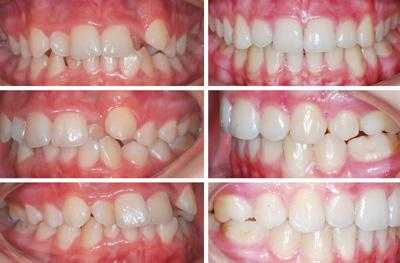

Завершенные клинические случаи дистального прикуса

Признаки дистального прикуса

Любой неправильный прикус определяется прежде всего по положению зубных рядов при смыкании. Но некоторые окклюзионные аномалии отражаются на внешности в целом: формируют черты лица, мимику, симметрию, влияют на положение тела.

Профиль до и после лечения дистального прикуса